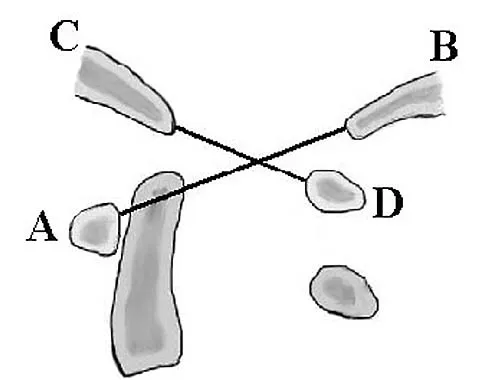

The safest surgical approach to the insertion of the tibial posterior cruciate ligament uses the interval between which of the following muscles?

Options:

- Semimembranosus and medial gastrocnemius

- Semimembranosus and semitendinosus

- Medial and lateral gastrocnemius

- Lateral gastrocnemius and biceps femoris tendon

- Popliteus and lateral gastrocnemius

Correct Answer: Semimembranosus and medial gastrocnemius

Explanation:

Burks and Schaffer described an approach to the tibial insertion of the posterior cruciate ligament that uses the interval between the semimembranosus and the medial gastrocnemius. The medial gastrocnemius muscle is retracted laterally and protects the neurovascular bundle. This approach is used to repair an avulsion of the posterior cruciate ligament tibial attachment or for performing a posterior cruciate ligament tibial inlay reconstruction. Berg EE: Posterior cruciate ligament tibial inlay reconstruction. Arthroscopy 1995;8:95-99.